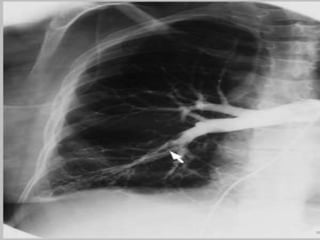

ChestXray

• Most patientswith pulmonary embolism haveabnormalbut nonspecific chest

radiographicfindings.

• Commonradiographic findings include atelectasis,pleuraleffusion, pulmonary

infiltrates, and mild elevation of ahemidiaphragm.

• Classicfindings of pulmonary infarction—such asHampton’s hump or decreased

vascularity (Westermark’s sign)—aresuggestivebut infrequent.

• Hampton humprefers to adome-shaped, pleurally-basedopacificationin the lung.

• Palasign isaprominent pulmonary artery that canbecausedeither by pulmonary

hypertensionthat developsor bydistension of the vesselby alarge pulmonary embolus.

• Westermark’ssign –peripheraloligemia.

• Anormal chest radiograph in apatient with otherwise unexplained acute dyspneaor

hypoxemia isstrongly suggestiveofembolism.

ChestXray • Most patientswithpulmonary embolism haveabnormalbut nonspecific chest radiographicfindings. • Commonradiographic findings include atelectasis,pleuraleffusion, pulmonary infiltrates, and mild elevation of ahemidiaphragm. • Classicfindings of pulmonary infarction—such asHampton’s hump or decreased vascularity (Westermark’s sign)—aresuggestivebut infrequent. • Hampton humprefers to adome-shaped, pleurally-basedopacificationin the lung. • Palasign isaprominent pulmonary artery that canbecausedeither by pulmonary hypertensionthat developsor bydistension of the vesselby alarge pulmonary embolus. • Westermark’ssign –peripheraloligemia. • Anormal chest radiograph in apatient with otherwise unexplained acute dyspneaor hypoxemia isstrongly suggestiveofembolism.